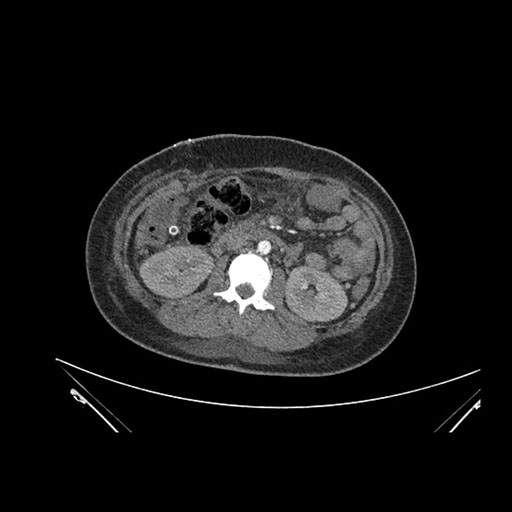

Imaging Analysis

Look through the patient's CT scan to identify any areas of concern for the necessary procedure.

Axial Arterial